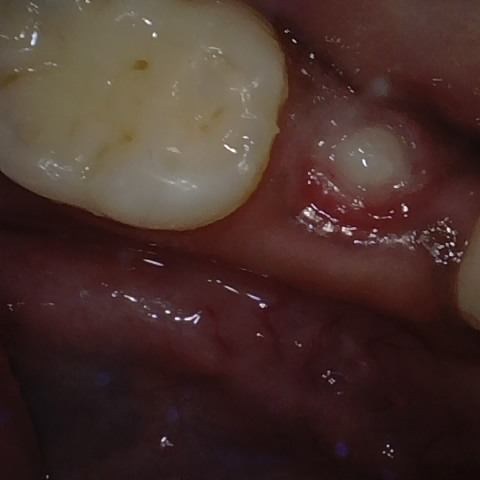

Annotated as "Good"